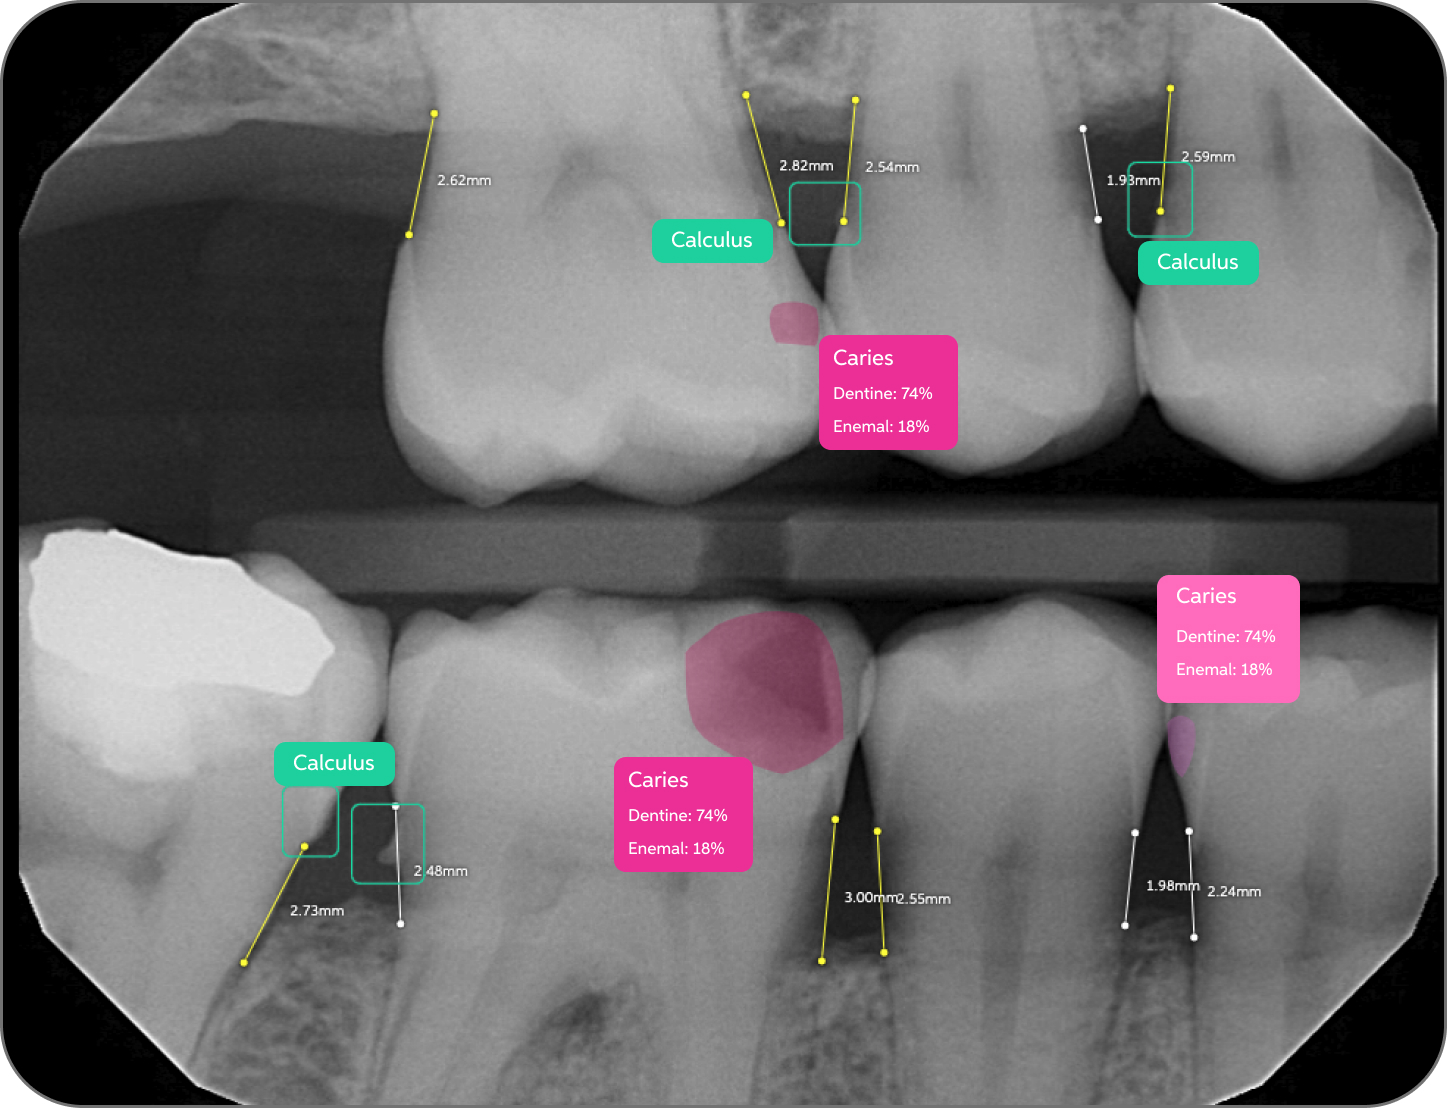

Pearl’s AI is trained on world's largest collection dental x-rays to detect a greater range of pathologies, existing restorations and natural anatomy than any solution of its kind, enabling 37% more accurate x-ray evaluations.

Color-coded detections, educational tooth part maps and quantitative results give patients an objective, clear and data-based foundation for trust in your findings––trust that boosts case acceptance by 24% on average.